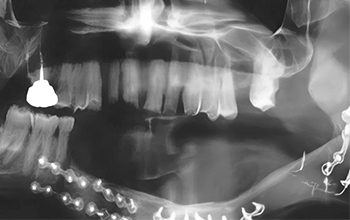

Fig. 03 : reconstruction mandibulaire par greffe libre de péroné.

Fig. 03 : reconstruction mandibulaire par greffe libre de péroné.

La chirurgie aboutit à des pertes de substances nécessitant des réparations plus ou moins importantes. Les petites pertes de substance, comme pour une tumeur T1, ne nécessiteront pas d’apport tissulaire. A contrario, les grandes pertes feront appel à des lambeaux pédiculés comme le grand pectoral, le grand dorsal ou des lambeaux libres tels que des greffes de péroné pour la reconstruction mandibulaire. Ces lambeaux assurant la survie du patient, la restauration des fonctions et l’esthétique.